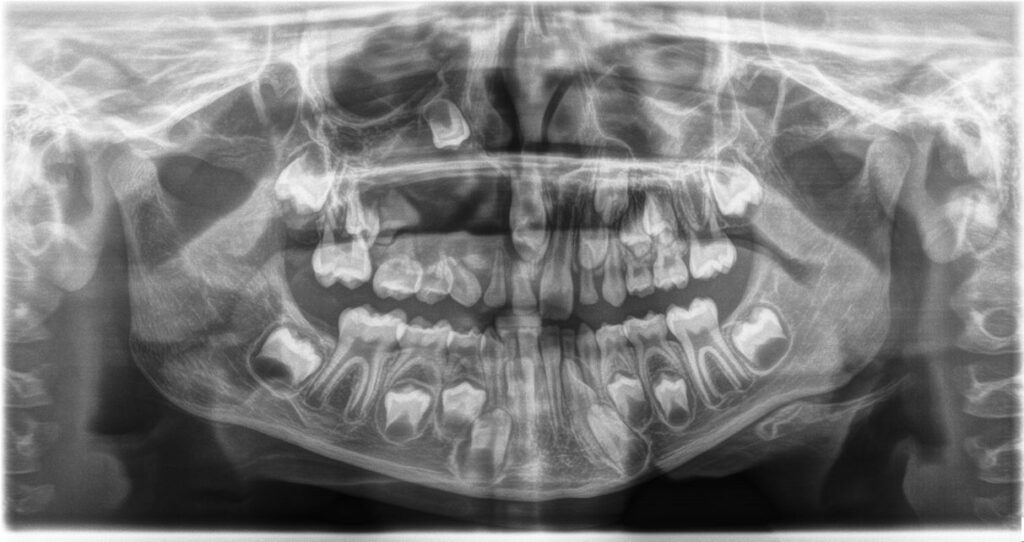

A 7-year-old girl with discolored teeth and caries.